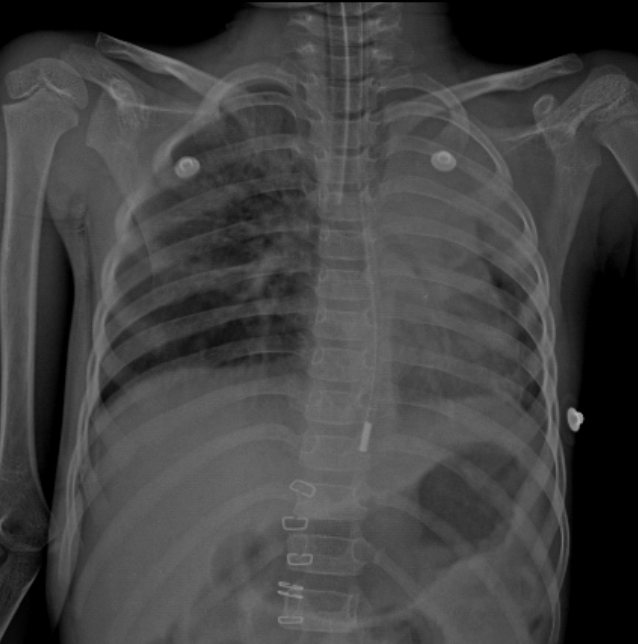

Q

In this CXR -Is the ETT Placed correctly?

No ETT it is a RMB intubation

Case courtesy of Aditya Shetty, <a>Radiopaedia.org</a>. From the case <a>rID: 26991</a>